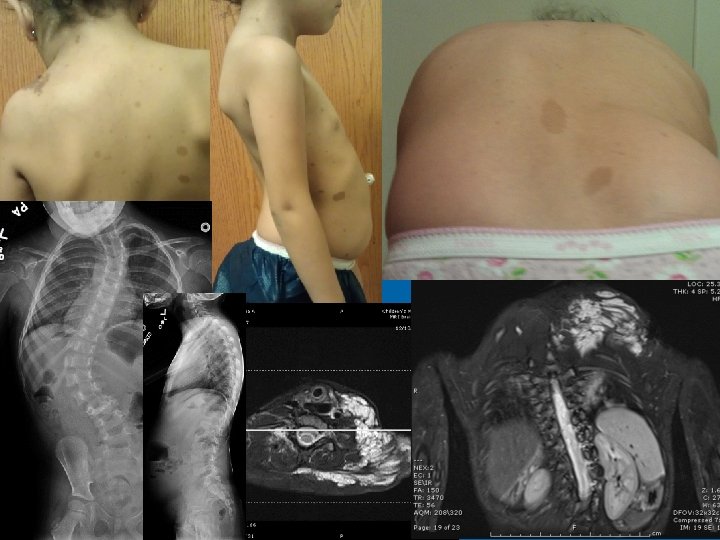

Pathophysiology of Dural Ectasia NF 1 • General primary mesodermal dysplasia • Weakness in the collagen through proliferation and invasion of NF 1 deficient fibroblasts • Atit 1999 • 30% have osteopenia due to haploinsufficiency • Osteomalacia, osteoporosis, vitamin D deficiency, stress fracture • CSF pulsations 23

NF 1 and Dural Ectasia • Frequently thoracic • Can be relatively protective, increased SAC • Posterior scalloping commonly associated with dural ectasia • Lateral and anterior scalloping commonly result of primary mesodermal dysplasia • Tsirikos AI 2004 • Anterior dural ectasia and dislocation of the spine • Winter 1991 28

Modi HN 2009 De Kleuver M 2004 29